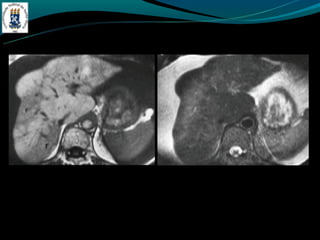

CIRROSE

NÓDULOS

- Nódulos regenerativos: 3-10mm, a maioria são isodensos, sinal

variável em T1, T2 hipo ou isointenso.

- Fibrose hepática confluente

- Áreas de fibrose semelhantes a massa, forma de cunha,

hipodensas, perda de volume da porção afetada do fígado

- São hiperintensas em T2 e hipo em T1.

CIRROSE NÓDULOS - Nódulos regenerativos: 3-10mm, a maioria são isodensos, sinal variável em T1, T2 hipo ou isointenso.

CIRROSE - Fibrose hepáticaconfluente - Áreas de fibrose semelhantes a massa, forma de cunha, hipodensas, perda de volume da porção afetada do fígado - São hiperintensas em T2 e hipo em T1.